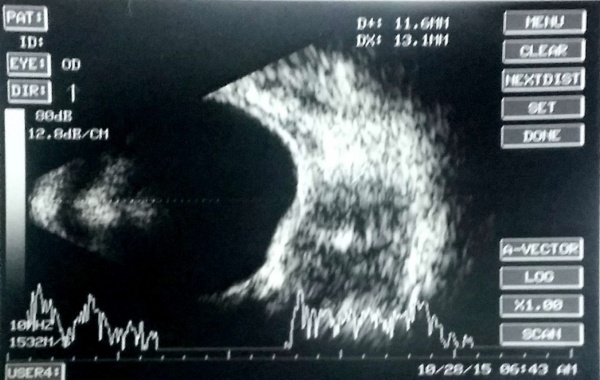

[The funnel RD is attached to the disc and is not showing after-movements with ocular movements.]

In cases of bullous retinal detachments with 'shifting fluid' (in sitting position the RD is inferior bullous and superior retina seems attached; in supine position, there is a total retinal detachment), it may be necessary to rule out an exudative retinal detachment (ERD). ERD usually shows subretinal echoe. A choroidal mass may be detectable, or the ultrasound may reveal another cause of the ERD (e.g., posterior scleritis, Vogt-Koyanagi-Harada syndrome).

A case of choroidal hemangioma[6] with exudative RD. Note the limited after-movements.